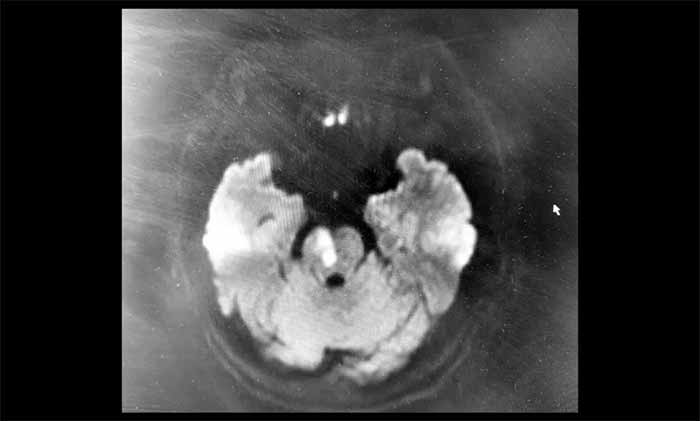

磁共振彌散加權(quán)成像(DWI)結(jié)果顯示:腦干區(qū)域可見(jiàn)明確的斑片狀高信號(hào)影,對(duì)應(yīng)的ADC圖呈低信號(hào)——這是新發(fā)腦干梗死的影像證據(jù)。腦動(dòng)脈成像同時(shí)提示血管輕度硬化,右側(cè)椎動(dòng)脈V4段纖細(xì)。基于對(duì)后循環(huán)缺血的深刻認(rèn)識(shí)和對(duì)影像細(xì)節(jié)的敏銳把握,潘登博士結(jié)合影像與臨床癥狀,迅速明確了診斷,為患者爭(zhēng)取了寶貴的治療時(shí)間。

“這位患者癥狀看似輕微,但DWI影像顯示腦干已發(fā)生急性缺血損傷。腦干結(jié)構(gòu)精細(xì)、功能關(guān)鍵,即使小范圍梗死也可能帶來(lái)嚴(yán)重后果,或是更重癥風(fēng)險(xiǎn)的前兆。”潘登博士說(shuō)。

▲ 腦干梗死